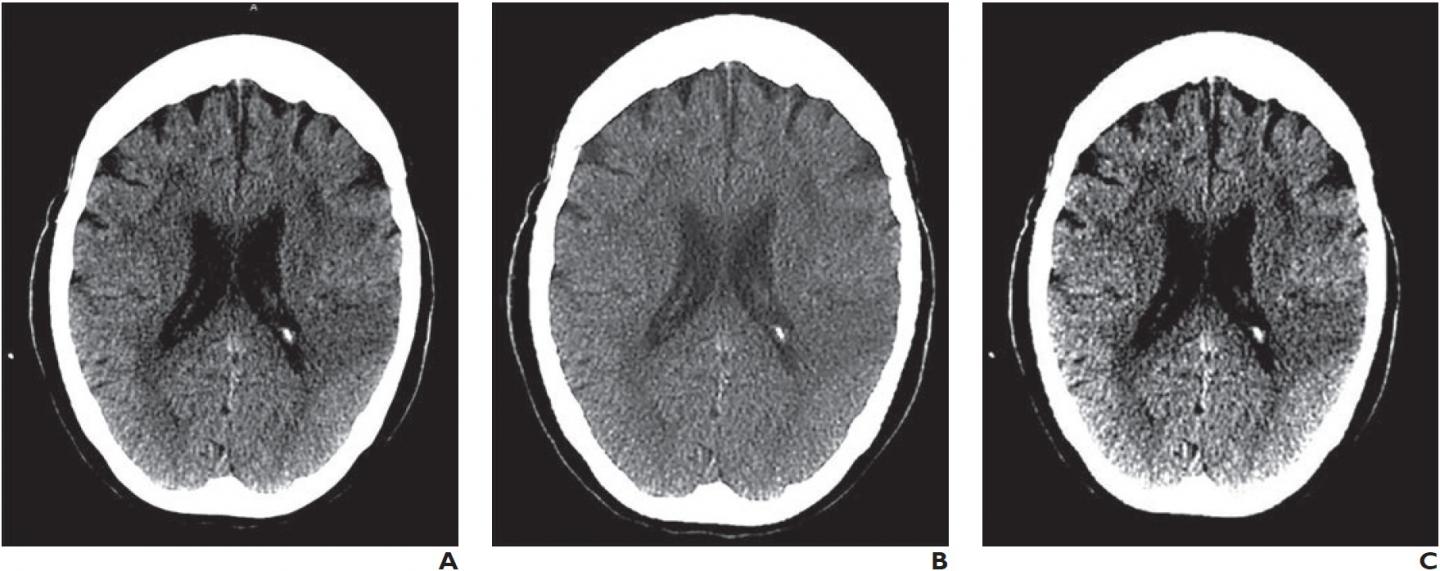

image: Barco E-2620 monitor (A), Samsung Galaxy S8 Plus smartphone (B), and Lenovo ThinkPad T460s laptop computer (C)

To assess reliability and accuracy of IV thrombolysis recommendations made after interpretation of head CT images of patients with acute stroke symptoms displayed on smartphone or laptop reading systems--compared with those made after interpretation of images displayed on a medical workstation monitor--Antonio J. Salazar at the University of Los Andes in Bogotá, Columbia utilized a factorial design with 188 patients, four radiologists, and three reading systems to produce 2256 interpretations.